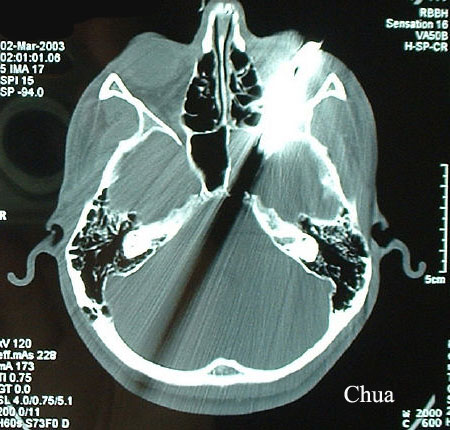

This teenager was harpooned

during a dispute. One of the prongs entered the lower orbit resulting in

globe perforation. CT scan showed the prongs narrowly missed the brain.